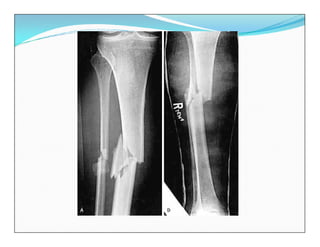

Fracturas diafisarias de la Tibia

EVALUACION RADIOLOGICA

 Rx Anteroposterior

 Rx Lateral

Toda la pierna incluyendo

rodilla y tobillo

 TAC

 RM

 Angiografía

Fracturas diafisarias dela Tibia EVALUACION RADIOLOGICA  Rx Anteroposterior  Rx Lateral Toda la pierna incluyendo rodilla y tobillo  TAC  RM  Angiografía